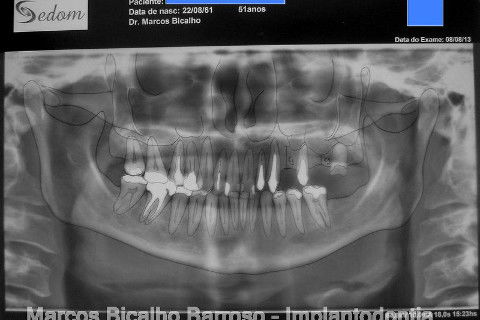

Paciente genêro feminino, 52 anos, procurou meus serviços para resolução de edentulismo parcial, insatisfação com ausência de dentes na região posterior esquerda da maxila, fratura de ponte fixa provisória...

Ao exame clínico já percebemos atrofia no rebordo, uma depressão na vestibular, indicação para enxerto ósseo e dente 27 com indicação para remoção. O plano de tratamento consistiu em levantamento de seio maxilar deste lado para possibilitar instalação de implante na região do 26 (não existe dente antagônico para oclusão com o 27), enxerto ósseo na vestibular do dente 24, aproveitamento do 22,23,25, em situação satisfatória, com indicação de confecção de novas coroas.